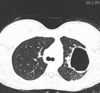

Birt-Hogg-Dubé syndrome or folliculin gene-associated syndrome is a genetic multisystemic disease mainly characterised by:

multiple lung cysts and secondary spontaneous pneumothoraces

multiple bilateral renal tumours (particularly chromophobe renal cell cancer and oncocytoma)

cutaneous manifestations (angiofibromas, perifollicular fibromas, acrochordons, fibrofolliculomas, etc.)

Birt-Hogg-Dubé syndrome carries an estimated 25% risk of renal cell carcinoma 12.

Radiographic features

Lung cysts in Birt-Hogg-Dubé syndrome are usually multiple and have a lower zone predominance 11. Cyst morphology tends to be variable within each patient, with cysts commonly oval or lentiform and septated when large 4. The presence of paramediastinal cysts when disproportionate in number or oval (floppy) in shape is another distinguishing characteristic 11.

Consider other cystic lung conditions such as:

lymphangioleiomyomatosis

cysts typically round, with diffuse (rather than lower zone) distribution

Langerhans cell histiocytosis

cysts variable in shape but classically co-existing with cavitating nodules. There is upper and mid zone predominance in size and number of cysts with sparing of costophrenic angles in contrast to lower lobe predominance in Birt Hogg Dube syndrome.